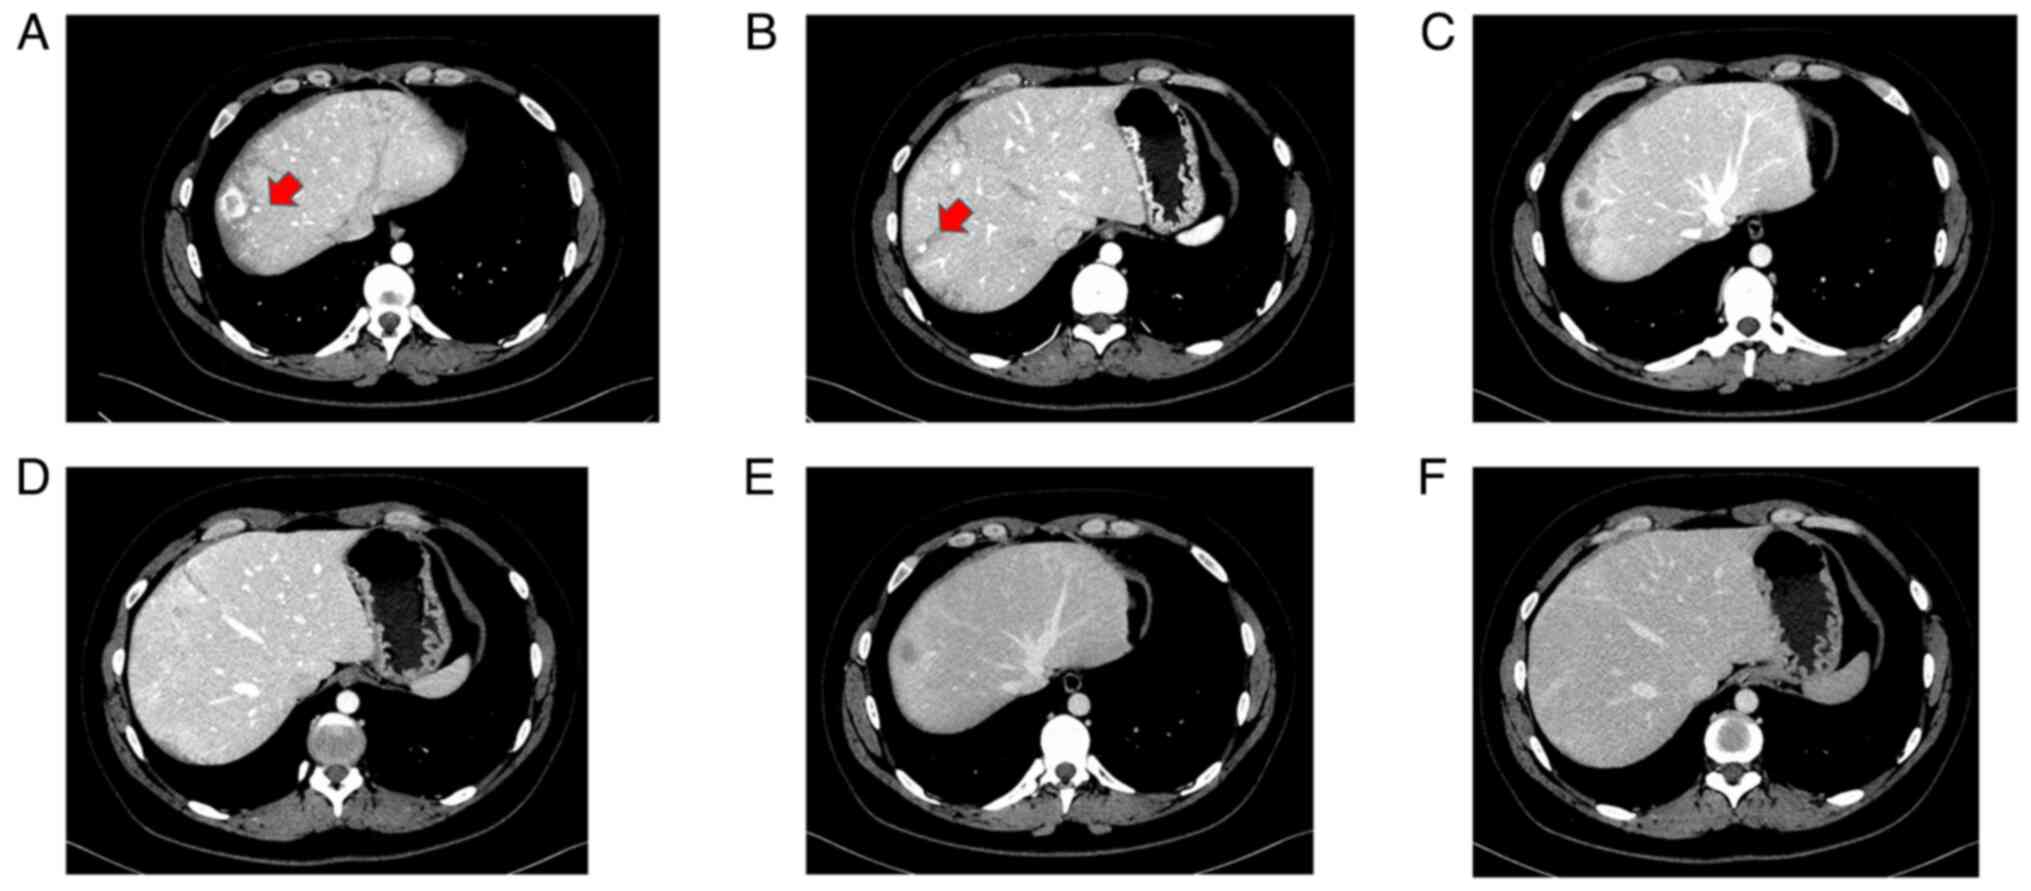

Because of the difficulty in confirming diagnosis using MRI alone, dynamic CT was performed with informed consent, which revealed that the main S8 tumor was contrast-enhanced in a ring shape in the early phase and washed out in the late phase (Fig. 4); it also showed low density on plain CT. A total of two small tumors near the primary tumor were also enhanced in the early phase of dynamic CT but were not identified in the late phase (Fig. 5). Upper and lower gastrointestinal endoscopy showed no malignant findings.

Figure 4

Dynamic CT findings of primary tumor. (A) In early phase, the main segment 8 tumor was contrast-enhanced in a ring shape (arrow). (B) In portal phase, the contrast medium of tumor was washed out (arrow). (C) In late phase, the contrast medium of tumor was washed out (arrow).

Figure 5

Dynamic CT findings of two small tumors. On the (A) left and (B) dorsal side near the primary tumor in S8, a small tumor was enhanced in the early phase (arrow). (C) Small tumor on the left side near the main tumor was not be identified in the late portal phase. (D) A small tumor on the dorsal side near the main tumor could not be identified in the late portal phase. (E) A small tumor on the left side near the main tumor could not be identified in the late phase. (F) A small tumor on the dorsal side near the main tumor could not be identified in the late phase.